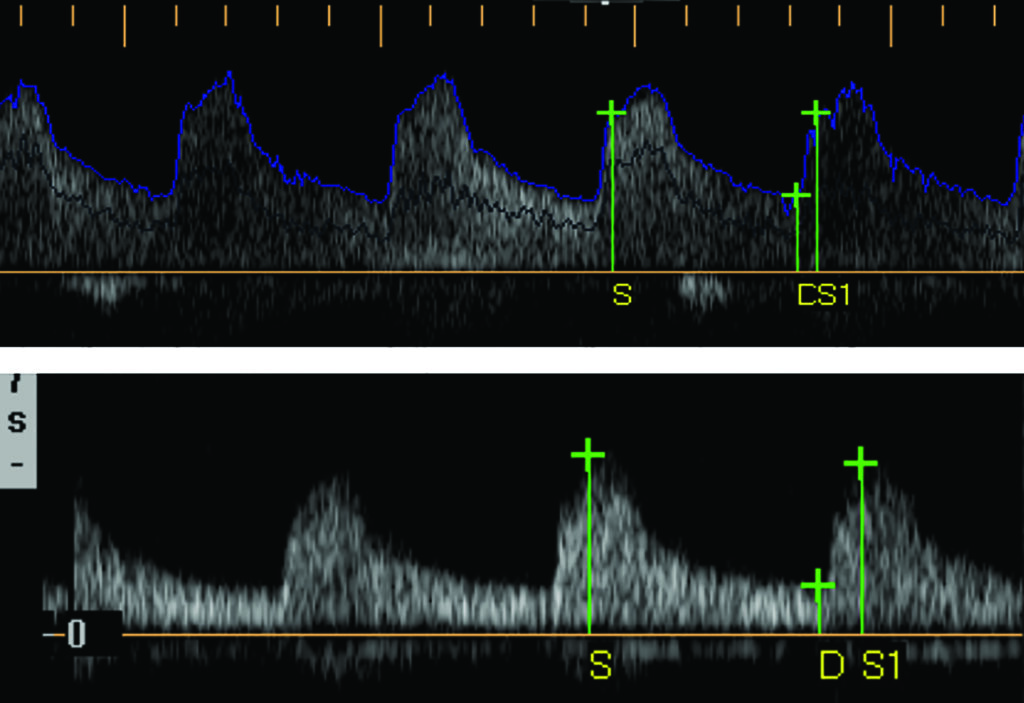

Determinación intrarenal. Los cambios en la forma de onda intrarenal son producto de la interacción entre la resistencia al flujo y la ductilidad arterial. Este fenómeno se traduce en el aumento del tiempo de aceleración (TA) y en la disminución del índice de resistencia (IR), parámetros que determinan indirectamente la presencia de estenosis. Realizando mediciones precisas (Fig. 1), el IR se calcula a partir de la fórmula:

IR = (Velocidad del pico sistólico – velocidad diastólica final) / Velocidad del pico sistólico

Cuando IR es <0,60, es sugestivo de estenosis de la arteria renal. El TA corresponde al tiempo que transcurrido desde diástole final hasta el primer pico sistólico y se diagnostica estenosis en el caso de que el resultado sea >0,90 seg (Fig. 2, Fig. 3).

Determinación extrarenal. Esta determinación se realiza midiendo la velocidad del pico sistólico y la velocidad diastólica final de la arteria renal a nivel de ostium, en el tercio medio y el hilio renal. También en este caso se calculan el índice de resistencia y el tiempo de aceleración, y deben realizarse no menos de tres determinaciones para confirmar el diagnóstico.